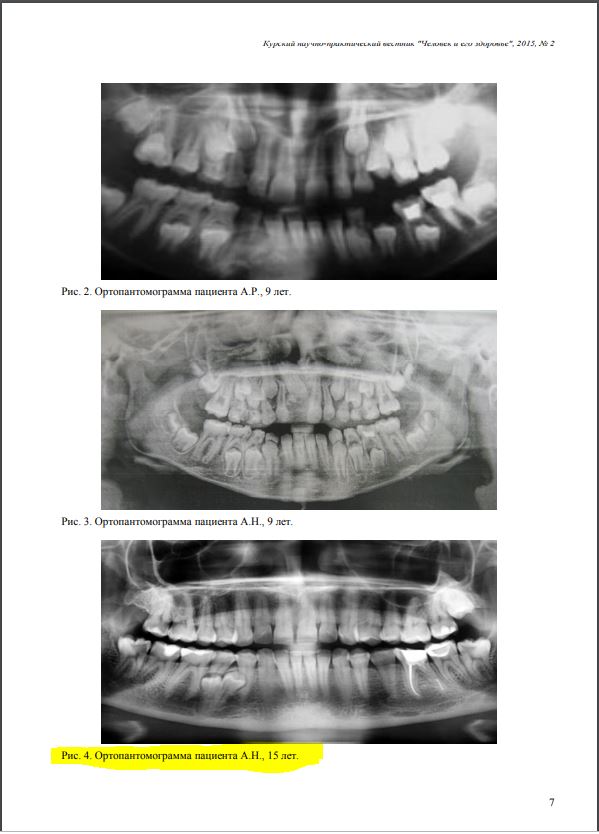

Во-первых, среди докторов нет чёткого представления о том, что считать периимплантитом. Можно ли назвать периимплантитом, например, вот такое?

Во-вторых, из-за неразберихи в терминологии и симптоматике, статистика перимплантитов — это, в общем-то, отсутствие статистики: одни Ыксперты утверждают, что признаки периимплантита развивается чуть ли не в 80% случаев имплантации, другие говорят о 10-20-50% и, как вы понимаете, такой разброс в цифрах — главный признак ненаучности методов подсчёта.

В-третьих, нет однозначного мнения о причинах развития периимплантита. Диапазон предположений слишком уж широк: от банальной перегрузки и плохой гигиены до специфической микрофлоры и генетической патологии. Также существуют определённые сложности с диагностикой: 99% периимплантитов протекают бессимптомно и выявляются случайно, во время рентгенологического обследования совсем, назначенного по совсем другому поводу.